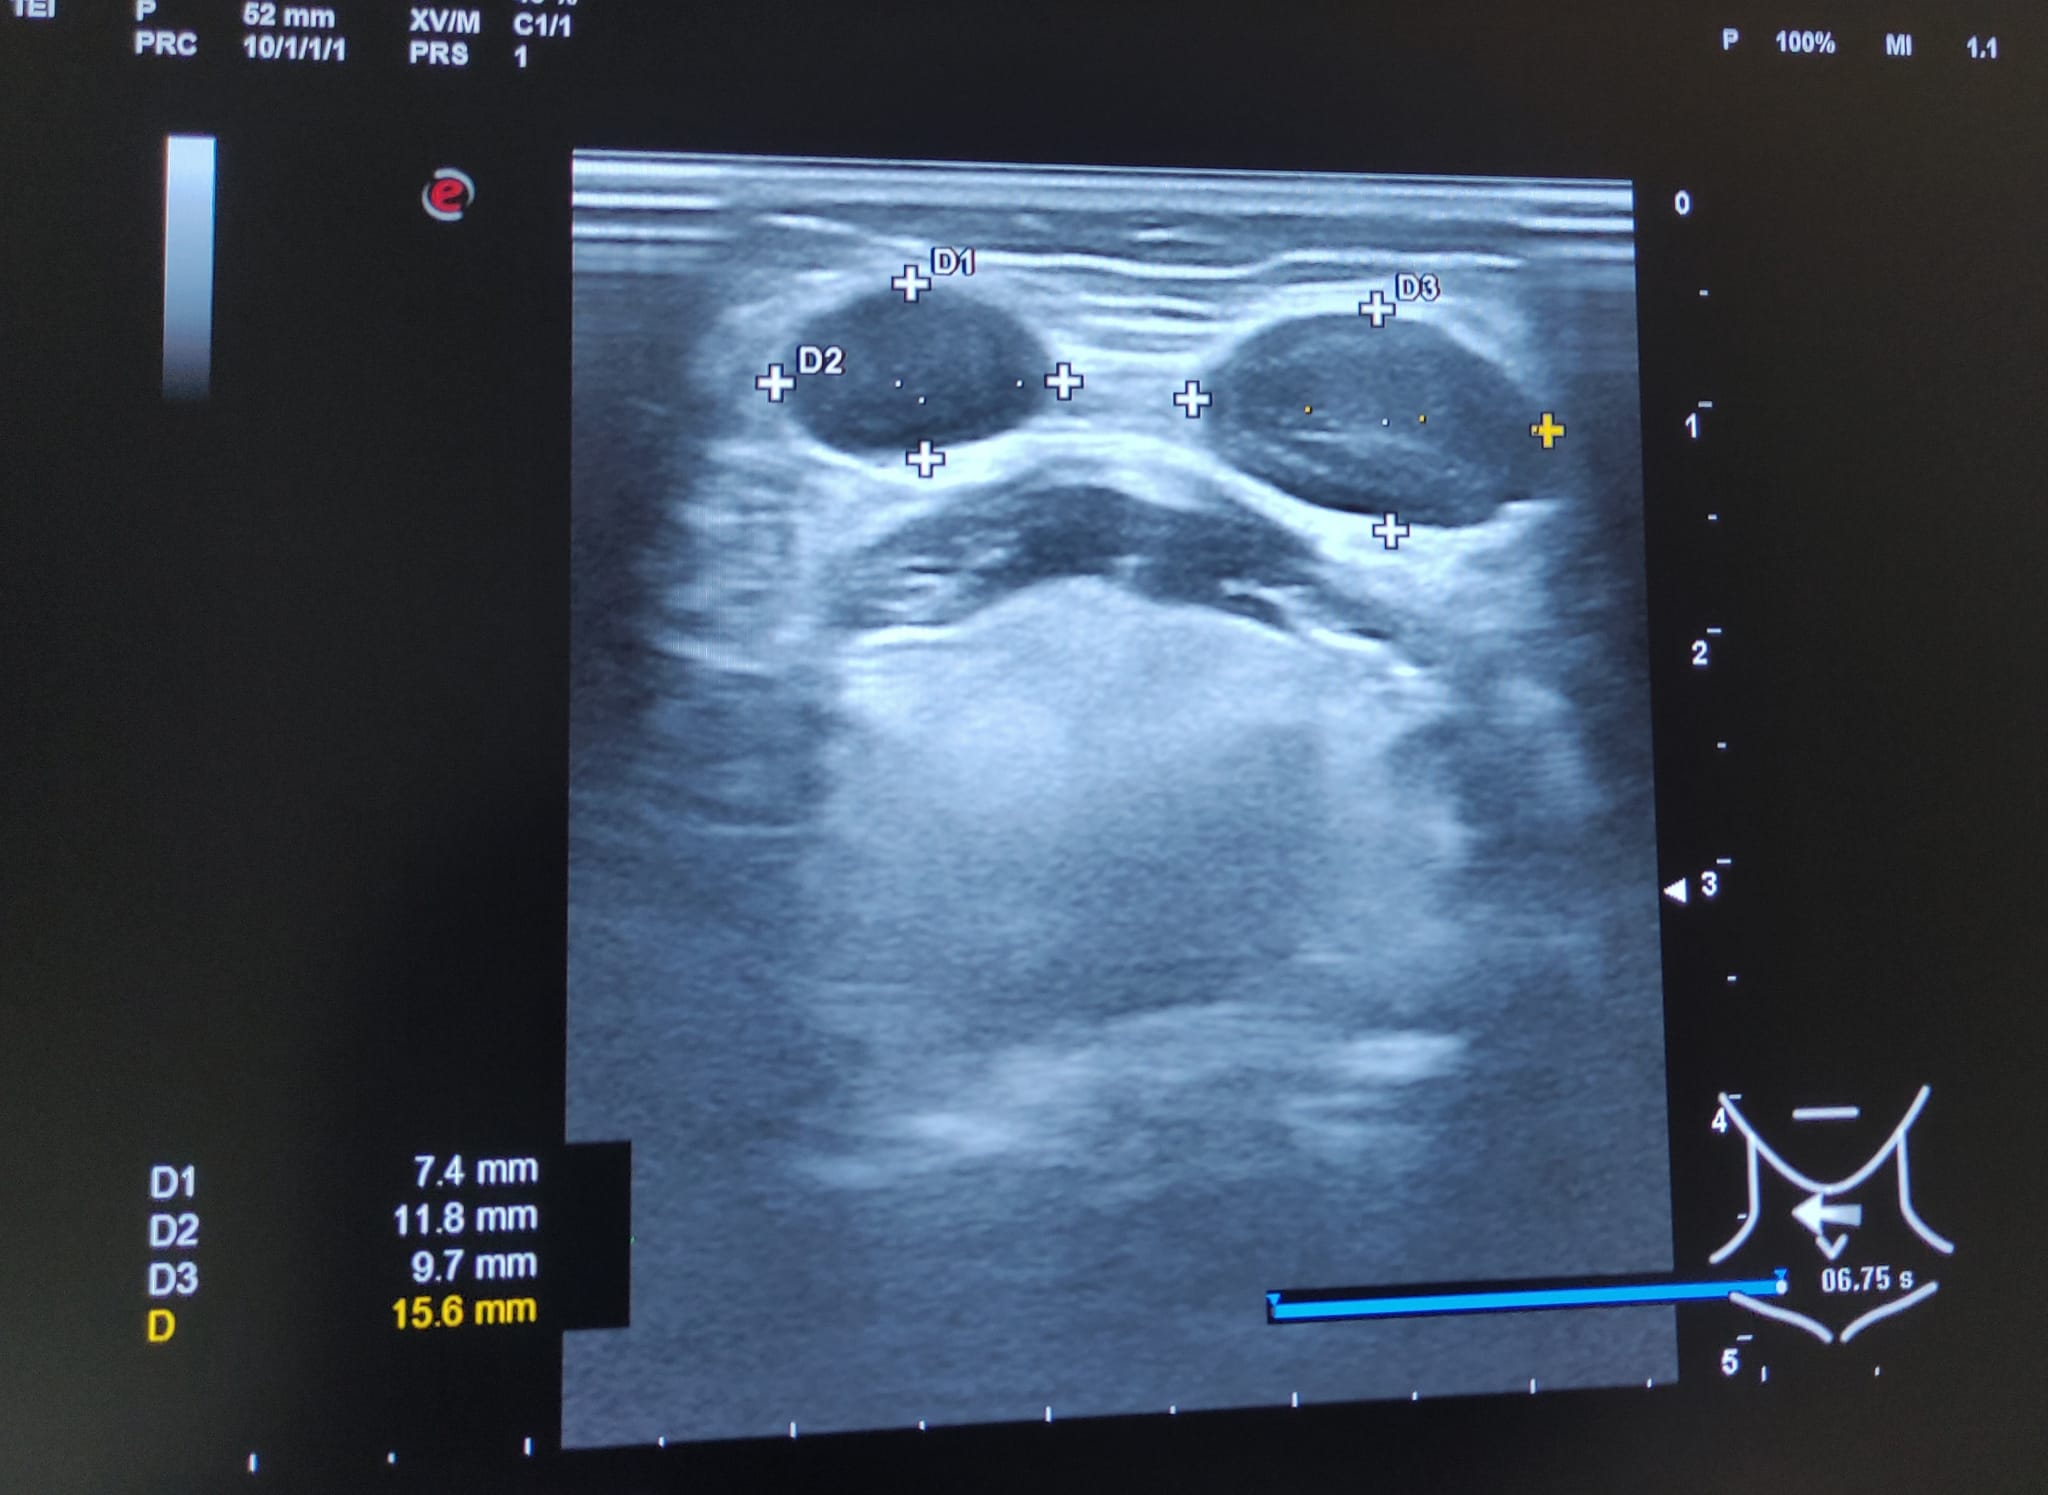

Múltiples adenopatías (más de 12) de varios tamaños siendo la mayor de 2 cm y de morfología redondeada, alguna sin hilio ni centro graso.

A los 3 meses se realiza nueva ecografía sin observar cambios significativos en las adenopatías ya visualizadas. Paciente permanece asintomática.